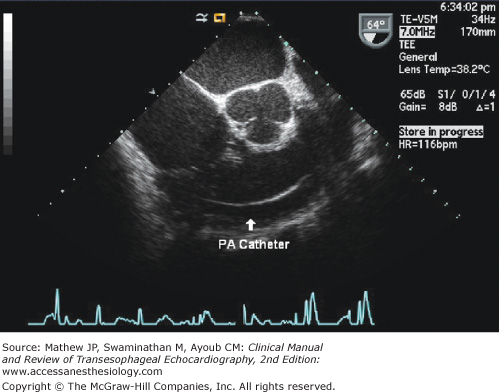

Two-dimensional examination of the tricuspid valve apparatus provides significant information regarding the underlying cause and mechanism of tricuspid regurgitation. The identification of anatomic abnormalities (eg, Ebstein’s anomaly), abnormal masses, annular dilatation, and noncoaptation (see Figure 10–3) are all essential to make a correct diagnosis. Pacemaker wires or catheters passing through the tricuspid orifice are readily visualized (Figure 10–6), and although uncommonly encountered with the right-sided valves,4 TEE is highly sensitive for the detection of vegetations.5 Movement of any of the leaflets beyond the plane of the tricuspid annulus inside the right atrium indicates the presence of tricuspid prolapse (Figure 10–7).6 Additionally, in patients with tricuspid valve prolapse, the leaflets and chordae are usually redundant and myxomatous. Features characteristic of Ebstein’s anomaly include apical displacement or “off-setting” of the hinge point attachment of the septal leaflet relative to that of the anterior mitral leaflet. A displacement index is easily produced by measuring the distance between the two hinge points and indexing to body surface area. This can be done in the midesophageal four-chamber view, and different angulations of the probe will help obtain the maximal difference. An indexed value greater than 8 mm/m squared7,8 or a nonindexed value of greater than 15 mm in children and 20 mm in adults,9 together with elongation of the anterior leaflet (the so-called “sail-like” or “curtain-like” appearance),10,11 tethering, and restricted leaflet motion,7 distinguish this congenital anomaly from other causes of tricuspid regurgitation. Additional echocardiographic features of Ebstein’s anomaly include apical displacement of the other leaflets, absence or fenestration of any of the leaflets, and “atrialization” of a part of the right ventricle.